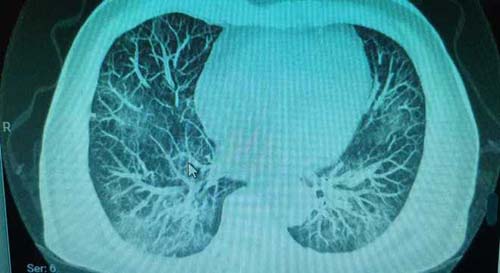

Pulmão de um paciente saudável

Arquivo pessoal